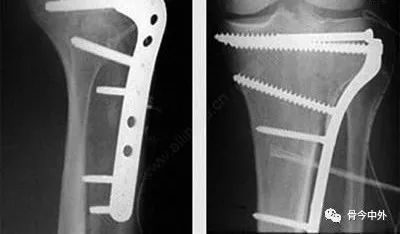

# تقنيات مبتكرة لتثبيت كسور نهاية عظم الكعبرة باستخدام الصفائح الراحية: دليل جراحي متكامل تُعتبر كسور نهاية عظم الكعبرة…